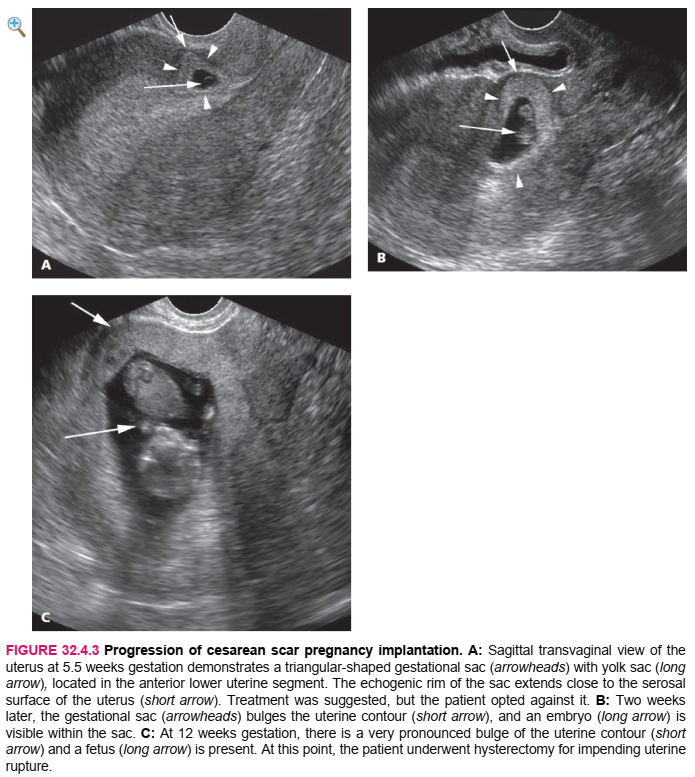

In a woman who has undergone prior cesarean delivery, ultrasound diagnosis of a pregnancy implanting deep into a cesarean scar is established when the gestational sac is located in the anterior lower uterine segment and the echogenic wall of the sac extends close to the serosal surface of the uterus (Figure 32.4.1). The gestational sac is often triangular in shape, pointing toward the anterior serosal surface of the uterus (Figure 32.4.1). There may be extensive blood flow around the gestational sac (Figure 32.4.2). If left untreated, sequential scans may demonstrate progressive bulging of the uterine contour (Figure 32.4.3).

Ở một phụ nữ đã từng sinh mổ trước đó, siêu âm chẩn đoán thai làm tổ sâu trong sẹo mổ lấy thai khi túi thai nằm ở đoạn trước dưới tử cung và thành hồi âm của túi kéo dài đến gần bề mặt thanh mạc của tử cung (Hình 32.4.1). Túi thai thường có hình tam giác, hướng về mặt thanh mạc trước của tử cung (Hình 32.4.1). Có thể có máu chảy nhiều quanh túi thai (Hình 32.4.2). Nếu không được điều trị, chụp quét tuần tự có thể cho thấy đường viền tử cung ngày càng phình ra (Hình 32.4.3).

HÌNH 32.4.3 Tiến triển của sẹo mổ lấy thai. A: Quang cảnh xuyên âm đạo Sagittal của tử cung ở tuổi thai 5,5 tuần có túi thai hình tam giác (đầu mũi tên) với túi noãn hoàng (dài mũi tên), nằm ở đoạn trước dưới tử cung. Vành hồi âm của túi kéo dài gần với thanh mạc bề mặt của tử cung (mũi tên ngắn). Điều trị đã được đề xuất, nhưng bệnh nhân đã từ chối nó. B: Hai tuần sau đó, túi thai (đầu mũi tên) phình ra theo đường viền tử cung (mũi tên ngắn), và một phôi thai (mũi tên dài) là có thể nhìn thấy trong túi. C: Khi thai 12 tuần tuổi, đường viền tử cung phồng lên rất rõ (ngắn mũi tên) và một bào thai (mũi tên dài) có mặt. Tại thời điểm này, bệnh nhân được phẫu thuật cắt tử cung để sắp xếp tử cung. vỡ ra.